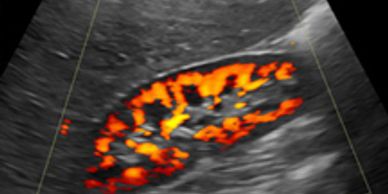

Renal artery duplex imaging evaluates blood flow velocities and patterns in the aorta and renal arteries. According to the American College of Radiology, "Ultrasound using grayscale imaging, Doppler spectral analysis, and color Doppler imaging is a proven and useful procedure for evaluating the renovascular system."